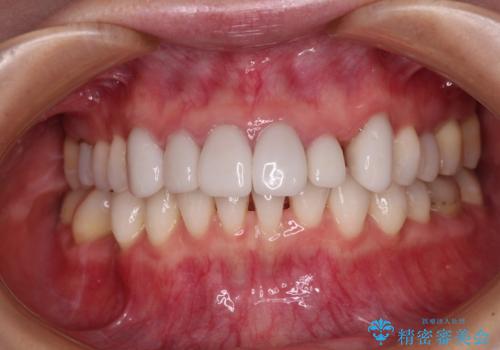

ワイヤー矯正の方が理想的な仕上がりとできる状態でしたが、上顎前歯にクラウンが装着されているため、インビザラインにて矯正治療を行うこととしました。

インビザラインのみで対応できないときにはワイヤー矯正を併用することとし、矯正治療後にはオールセラミッククラウンによる補綴治療を行うこととしました。

矯正治療自体はインビザラインで満足のいく仕上がりとなりました。

前歯は根管治療が必要となり、元々舌側に入り込んでいた左上2番目の歯は歯周外科処置により歯肉ラインを整えることとしました。

欠損部位は傾斜歯軸を起き上がらせることができたため、オールセラミッククブリッジにて補綴治療を行いました。